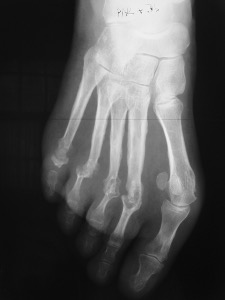

Polyarthrite Rhumatoïde : atteinte de tout l’avant-pied

Polyarthrite Rhumatoïde de l’avant-pied

La spécificité de l’hallux valgus rhumatoïde réside dans l’atteinte simultanée et réciproque de l’ensemble des éléments normalement en équilibre. On peut observer une synovite articulaire de la première articulation métatarso-phalangienne (MTP1) et bursite sous-cutanée par conflit avec les chaussures. Pour les métatarsiens voisins appelés les rayons latéraux, l’affaiblissement de l’ensemble des structures en équilibre aboutit au relâchement et à l’étalement des rayons latéraux.

Ce terme désigne la déformation en griffe des orteils latéraux avec (sub)luxation dorsale et déviation latérale (vers l’extérieur) des MTP. Ce phénomène nait de l’étalement des rayons latéraux et des griffes d’orteils dont la genèse est décrite plus haut.

Avant-pied triangulaire

Il est la somme de quatre atteintes élémentaires qui interagissent et s’amplifient réciproquement : hallux valgus, étalement des rayons latéraux, et griffes des orteils. A cela s’ajoute un quintus varus, véritable « hallux valgus en miroir » du cinquième rayon.

Les patients se plaignent d’une gêne au chaussage par confit avec les bords des premier et cinquième orteils, mais également avec le dos des orteils rétractés en griffes. Des métatarsalgies sont également présentes, tant par transfert de charge que par bursite intermétatarsienne ou par arthrite inflammatoire des MTP.